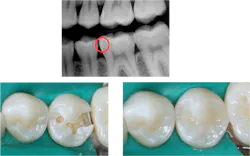

General dentists place numerous composites every day. The clinical longevity of composites is well known to be far shorter than that of amalgam restorations (figure 1). Several reasons relate to their short lifespan, including 2% shrinkage producing microscopically open margins on all restorations, no cariostatic activity provided by composite materials, inadequate curing accomplished by many dentists, occlusal wear, and other issues.

Since composite restorations are the most-used dental restoration type, and their inadequacies are obvious, this topic should be the highest priority for companies producing these products and for government agencies funding research. Our patients need nonshrinking, cariostatic, esthetic materials providing long-term service immediately!